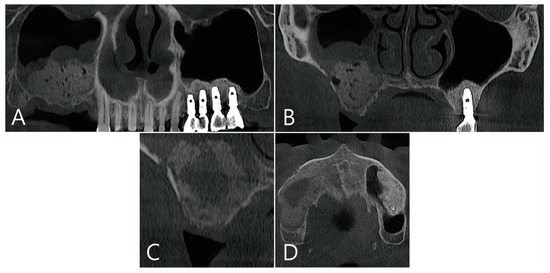

In the CBCT image taken immediately after the maxillary sinus bone graft, a thickened sinus membrane was observed on top of the bone graft material, and there was no leakage of the bone graft material (Figure 8A,B). In the CBCT image taken 6 months after surgery, a large grafting void was observed in the bone graft area which showed a cystic appearance (Figure 8C,D).

Figure 8. Case 3. CBCT images taken immediately after maxillary sinus bone graft: (A) On the panoramic image of CBCT, a thickened mucosa on the sinus floor was observed above the bone graft; (B) Coronal image of the CBCT. (C,D) Images of the CBCT taken 6 months after surgery: (C) in the coronal image of the CBCT, large grafting voids with a cystic appearance were observed; (D) a well-defined radiolucent appearance was observed on an axial image of the CBCT.